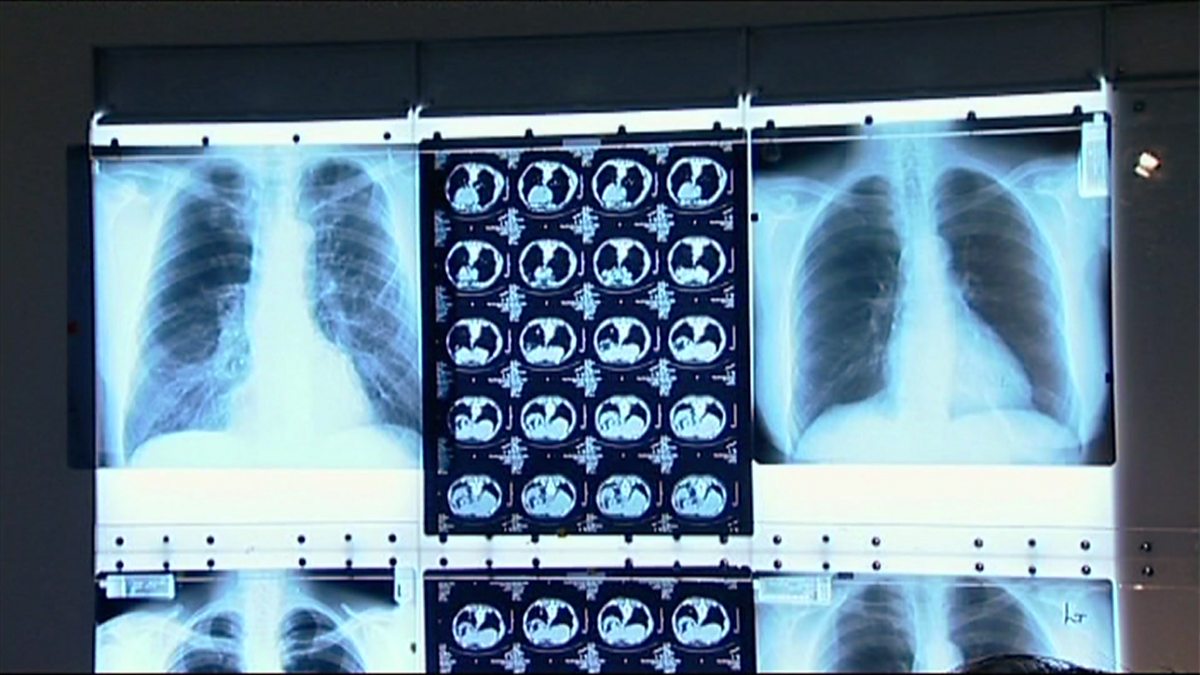

Tackling drug-resistant TB

Health experts are tackling an increase in highly infectious drug-resistant TB in London.